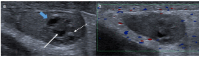

Pre- and post-pubertal testicular tumors are two distinct entities in terms of epidemiology, diagnosis and treatment. Most pre-pubertal tumors are benign; the most frequent are teratomas, and the most common malignant tumors are yolk-sac tumors. Post-pubertal tumors are similar to those found in adults and are more likely to be malignant. Imaging plays a pivotal role in the diagnosis, staging and follow-up. The appearance on ultrasonography (US) is especially helpful to differentiate benign lesions that could be candidates for testis-sparing surgery from malignant ones that require radical orchidectomy. Some specific imaging patterns are described for benign lesions: epidermoid cysts, mature cystic teratomas and Leydig-cell tumors. Benign tumors tend to be well-circumscribed, with decreased Doppler flow on US, but malignancy should be suspected when US shows an inhomogeneous, not-well-described lesion with internal blood flow. Imaging features should always be interpreted in combination with clinical and biological data including serum levels of tumor markers and even intra-operative frozen sections in case of conservative surgery to raise any concerns of malignity. This review provides an overview of imaging features of the most frequent testicular and para-testicular tumor types in children and the value of imaging in disease staging and monitoring children with testicular tumors or risk factors for testicular tumors.